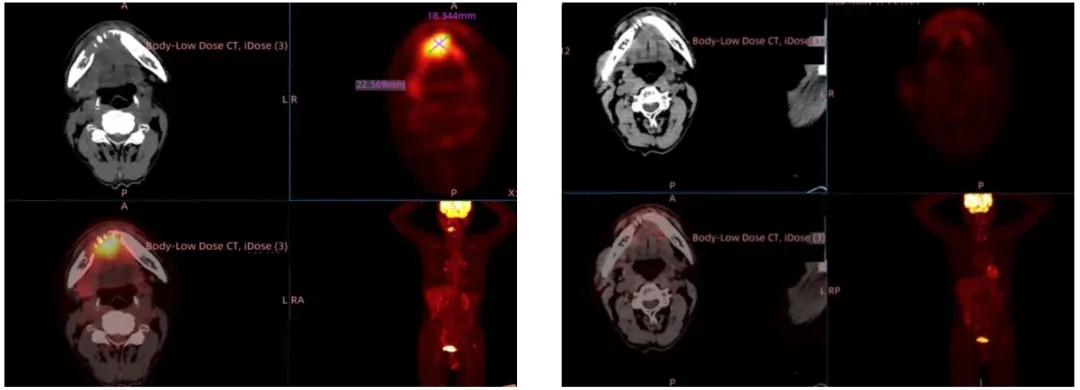

案例2(Ⅳ级脑胶质瘤):2025年SITC大会上,苏州大学附属第二医院与君赛生物联合公布I期临床试验(NCT04943913)振奋数据:一位确诊恶性程度最高的胶质母细胞瘤亚型的56岁男性患者,术后经Stupp方案、两次CAR-T治疗均失败。2023年末入组临床后,研究人员从其手术标本中制备TIL(T细胞占比99.92%,CD8⁺T细胞占比97.85%),12月完成输注。结果显示:GC101TIL细胞输注4周后,2.8cm复发病灶完全清零,疗效判定为完全缓解(CR);截至2025年6月,患者持续完全缓解超1.4年,已回归正常生活。

▲图源“JUNCELL”,版权归原作者所有,如无意中侵犯了知识产权,请联系我们删除